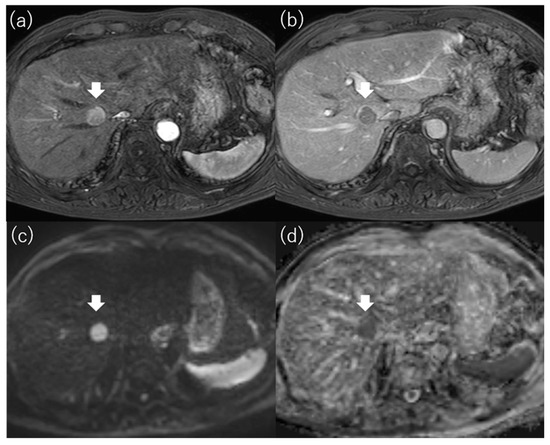

4.3. Diffusion-Weighted Imaging

- Mori, Y.; Tamai, H.; Shingaki, N.; Moribata, K.; Deguchi, H.; Ueda, K.; Inoue, I.; Maekita, T.; Iguchi, M.; Kato, J.; et al. Signal intensity of small hepatocellular carcinoma on apparent diffusion coefficient mapping and outcome after radiofrequency ablation. Hepatol. Res. Off. J. Jpn. Soc. Hepatol. 2015, 45, 75–87. [Google Scholar] [CrossRef]

- Mori, Y.; Tamai, H.; Shingaki, N.; Hayami, S.; Ueno, M.; Maeda, Y.; Moribata, K.; Deguchi, H.; Niwa, T.; Inoue, I.; et al. Hypointense hepatocellular carcinomas on apparent diffusion coefficient mapping: Pathological features and metastatic recurrence after hepatectomy. Hepatol. Res. Off. J. Jpn. Soc. Hepatol. 2016, 46, 634–641. [Google Scholar] [CrossRef]

| Mori et al. [68] | 136 | ≤3 tumors and ≤3 cm | RFA | Outcome (recurrence, OS) | Hypointensity on the ADC map was one of the independent factors for recurrence (HR, 2.651; 95% CI, 1.530–4.593; p = 0.001), local recurrence (HR, 5.602; 95% CI, 1.526–20.568; p = 0.009), critical recurrence (HR, 2.555; 95% CI, 1.171–5.571; p = 0.018), and survival (HR, 2.945; 95% CI, 1.124–7.721; p = 0.028). |

| Mori et al. [69] | 52 | Solitary and ≤5 cm | LR | Outcome (recurrence) | Hypointensity on the ADC map was one of the independent factors for metastatic recurrence (HR, 12.279; 95% CI, 1.486–101.48; p = 0.020). |